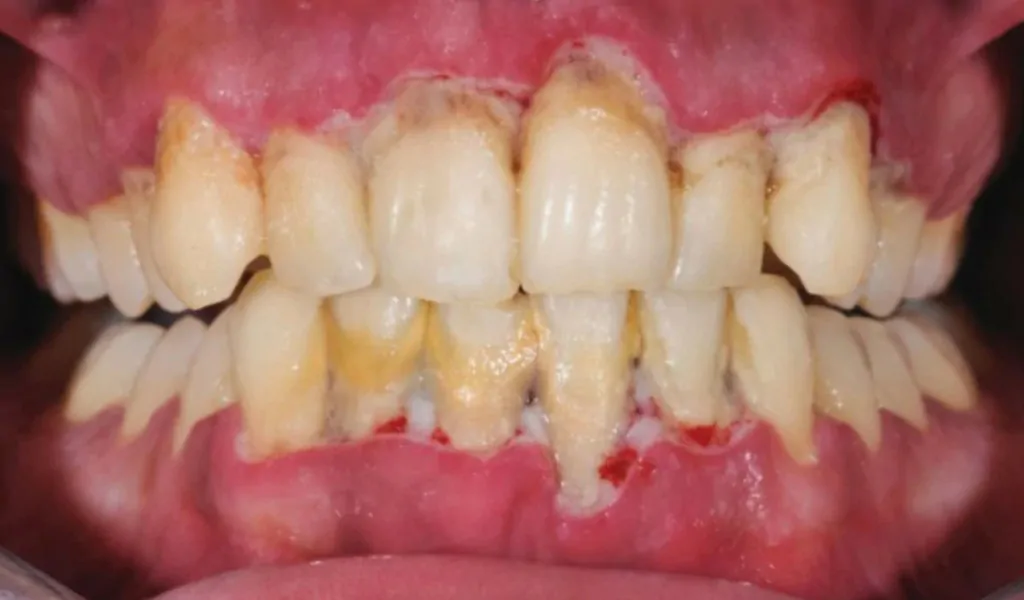

3. Menghindari Penyakit Gusi

Kelebihan Scaling Gigi yang seterusnya adalah bagi menghindari penyakit gusi. Mungkin ada rasa ia tiada kaitan tapi sebenarnya karang gigi boleh menyebabkan penyakit gusi seperti berdarah dan bengkak.

Jika tidak dirawat buat jangka panjang, boleh menyebabkan menjadi longgar atau nama lain kita panggil ‘Periodontitis’.